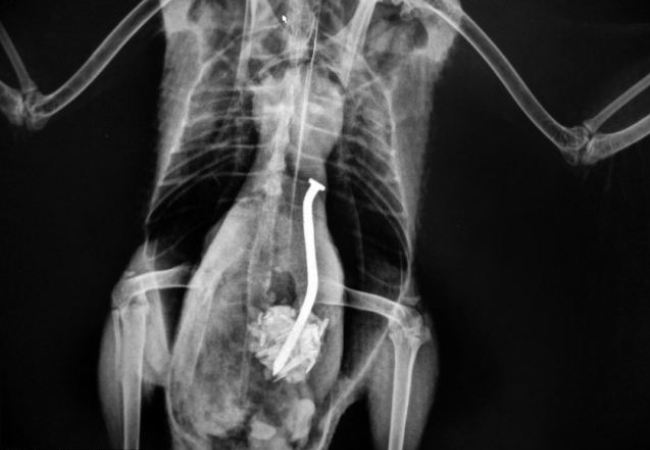

Кроме этого многие считают, что беспородные кошки и собаки не могут заражаться или переносят болезни в очень легкой форме. Это мнение ошибочное, поскольку они также тяжело болеют и очень часто умирают. Именно поэтому, всех домашних любимцев необходимо своевременно и правильно вакцинировать. Собакам вводят препараты от чумы, инфекционного гепатита, лептоспироза коронавирусного инфекционного энтерита, парагриппа и бешенства. Также можно провести рентген легких у кошек.